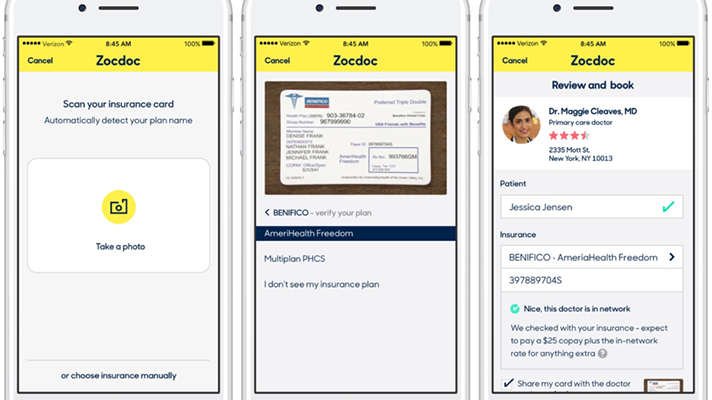

Nuance’s new technology aims to enhance interactions between patients and caregivers to both improve the consumer experience and reduce physician burnout.

Nuance Communications and Epic are partnering to integrate the artificial intelligence capabilities of Nuance's computer-assisted physician documentation tool into the Epic NoteReader module for clinical documentation improvement. Epic President Carl Dvorak explained that embedding the CAPD tool within Epic, the companies said physicians can get feedback at the point of care as provider organizations work to improve severity-adjusted quality scores and better understand reimbursement and risk adjustment factors to improve care management.